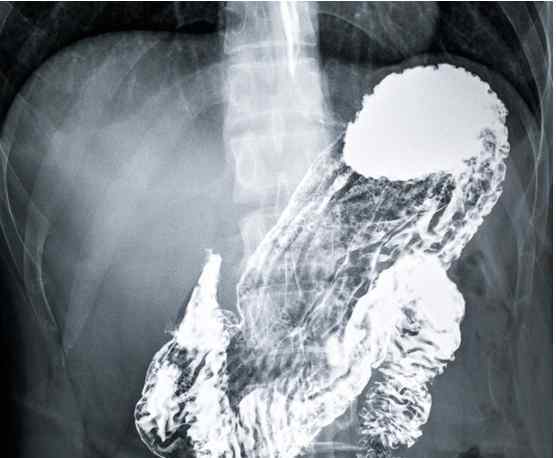

钡餐造影是指以硫酸钡混悬液为造影剂,口服进入人体消化道,在X线照射下显示消化道是否患病的影像检查方法。硫酸钡混悬液不溶于水和脂肪,不能被人体胃肠道吸收,基本无毒副作用。

钡餐主要通过观察外形来判断,容易耐受,但不如胃镜准确,容易误诊。